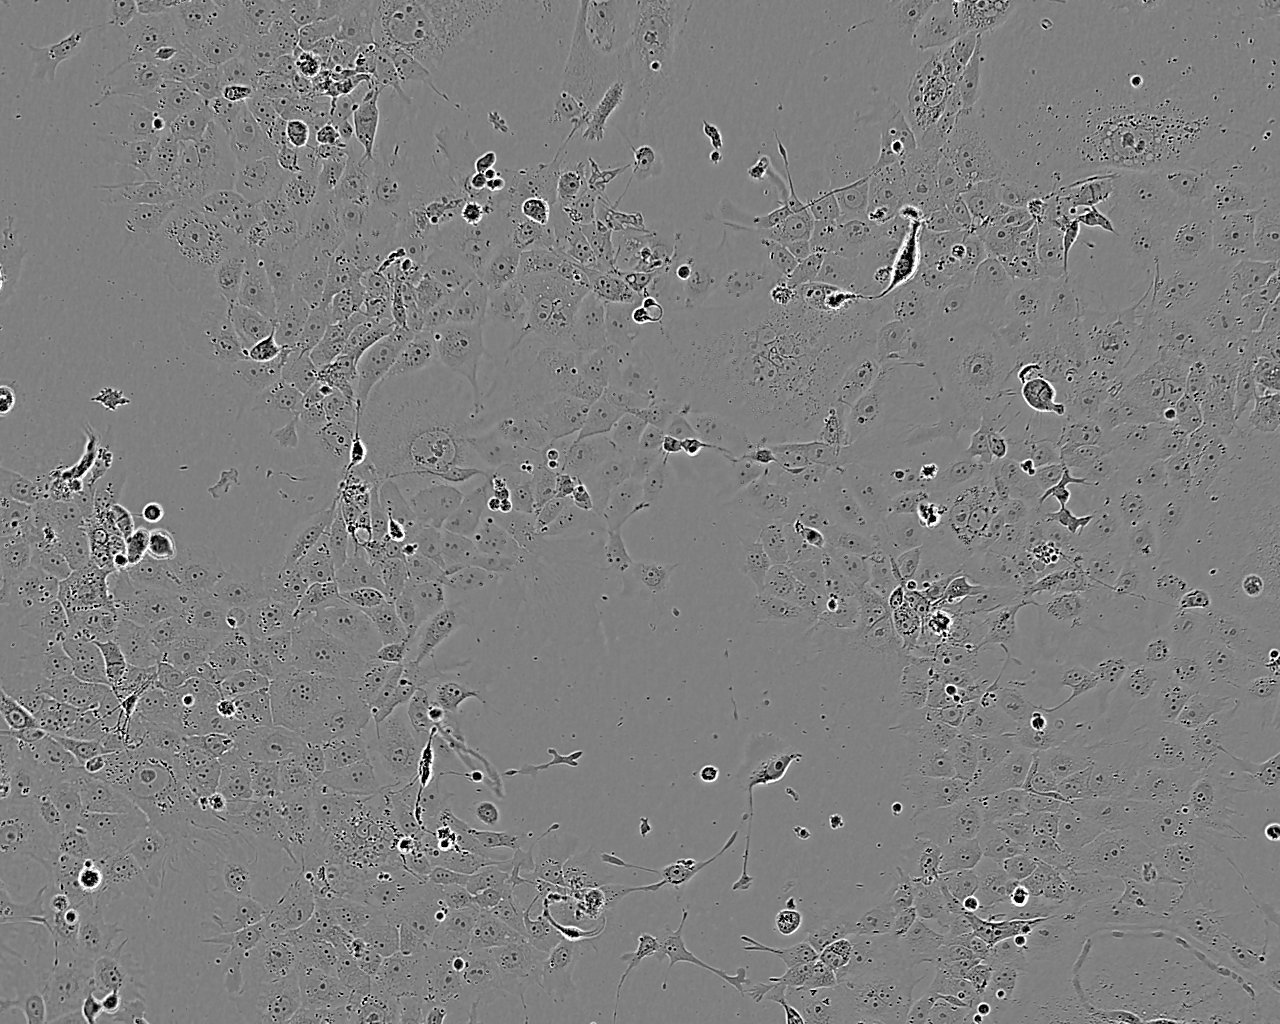

1.2B4 is a hybrid cell line formed by the electrofusion of a primary culture of human pancreatic islets with HuP-T3, a human pancreatic carcinoma cell line (ECACC catalogue number 93121055). 1.2B4 has been shown to be tumourigenic when transplanted into a SCID mouse host. The cell line has applications in the study of pancreatic cell biology. 1.2B4 cells provide a method of producing pure insulin secreting cells when stimulated (please see attached protocols for the stimulation of insulin secretion).. This is an alternative to the use of primary tissue in cell transplantation therapies for type 1 diabetes.

1.2B4 cells have been shown to express insulin, glucokinase and IAPP by immunocytochemistry. These cells express the GLUT1 glucose transporter.

Epitheloid

Split sub-confluent cultures (70-80%) 1:2 to 1:6 i.e. seeding at 2-4 x 10⁴ cells/cm² using 0.05% trypsin or trypsin/EDTA; 5% CO₂; 37°C. Population doubling approx 20hrs. At confluence 10⁵ cells/cm² can be expected.

Adherent